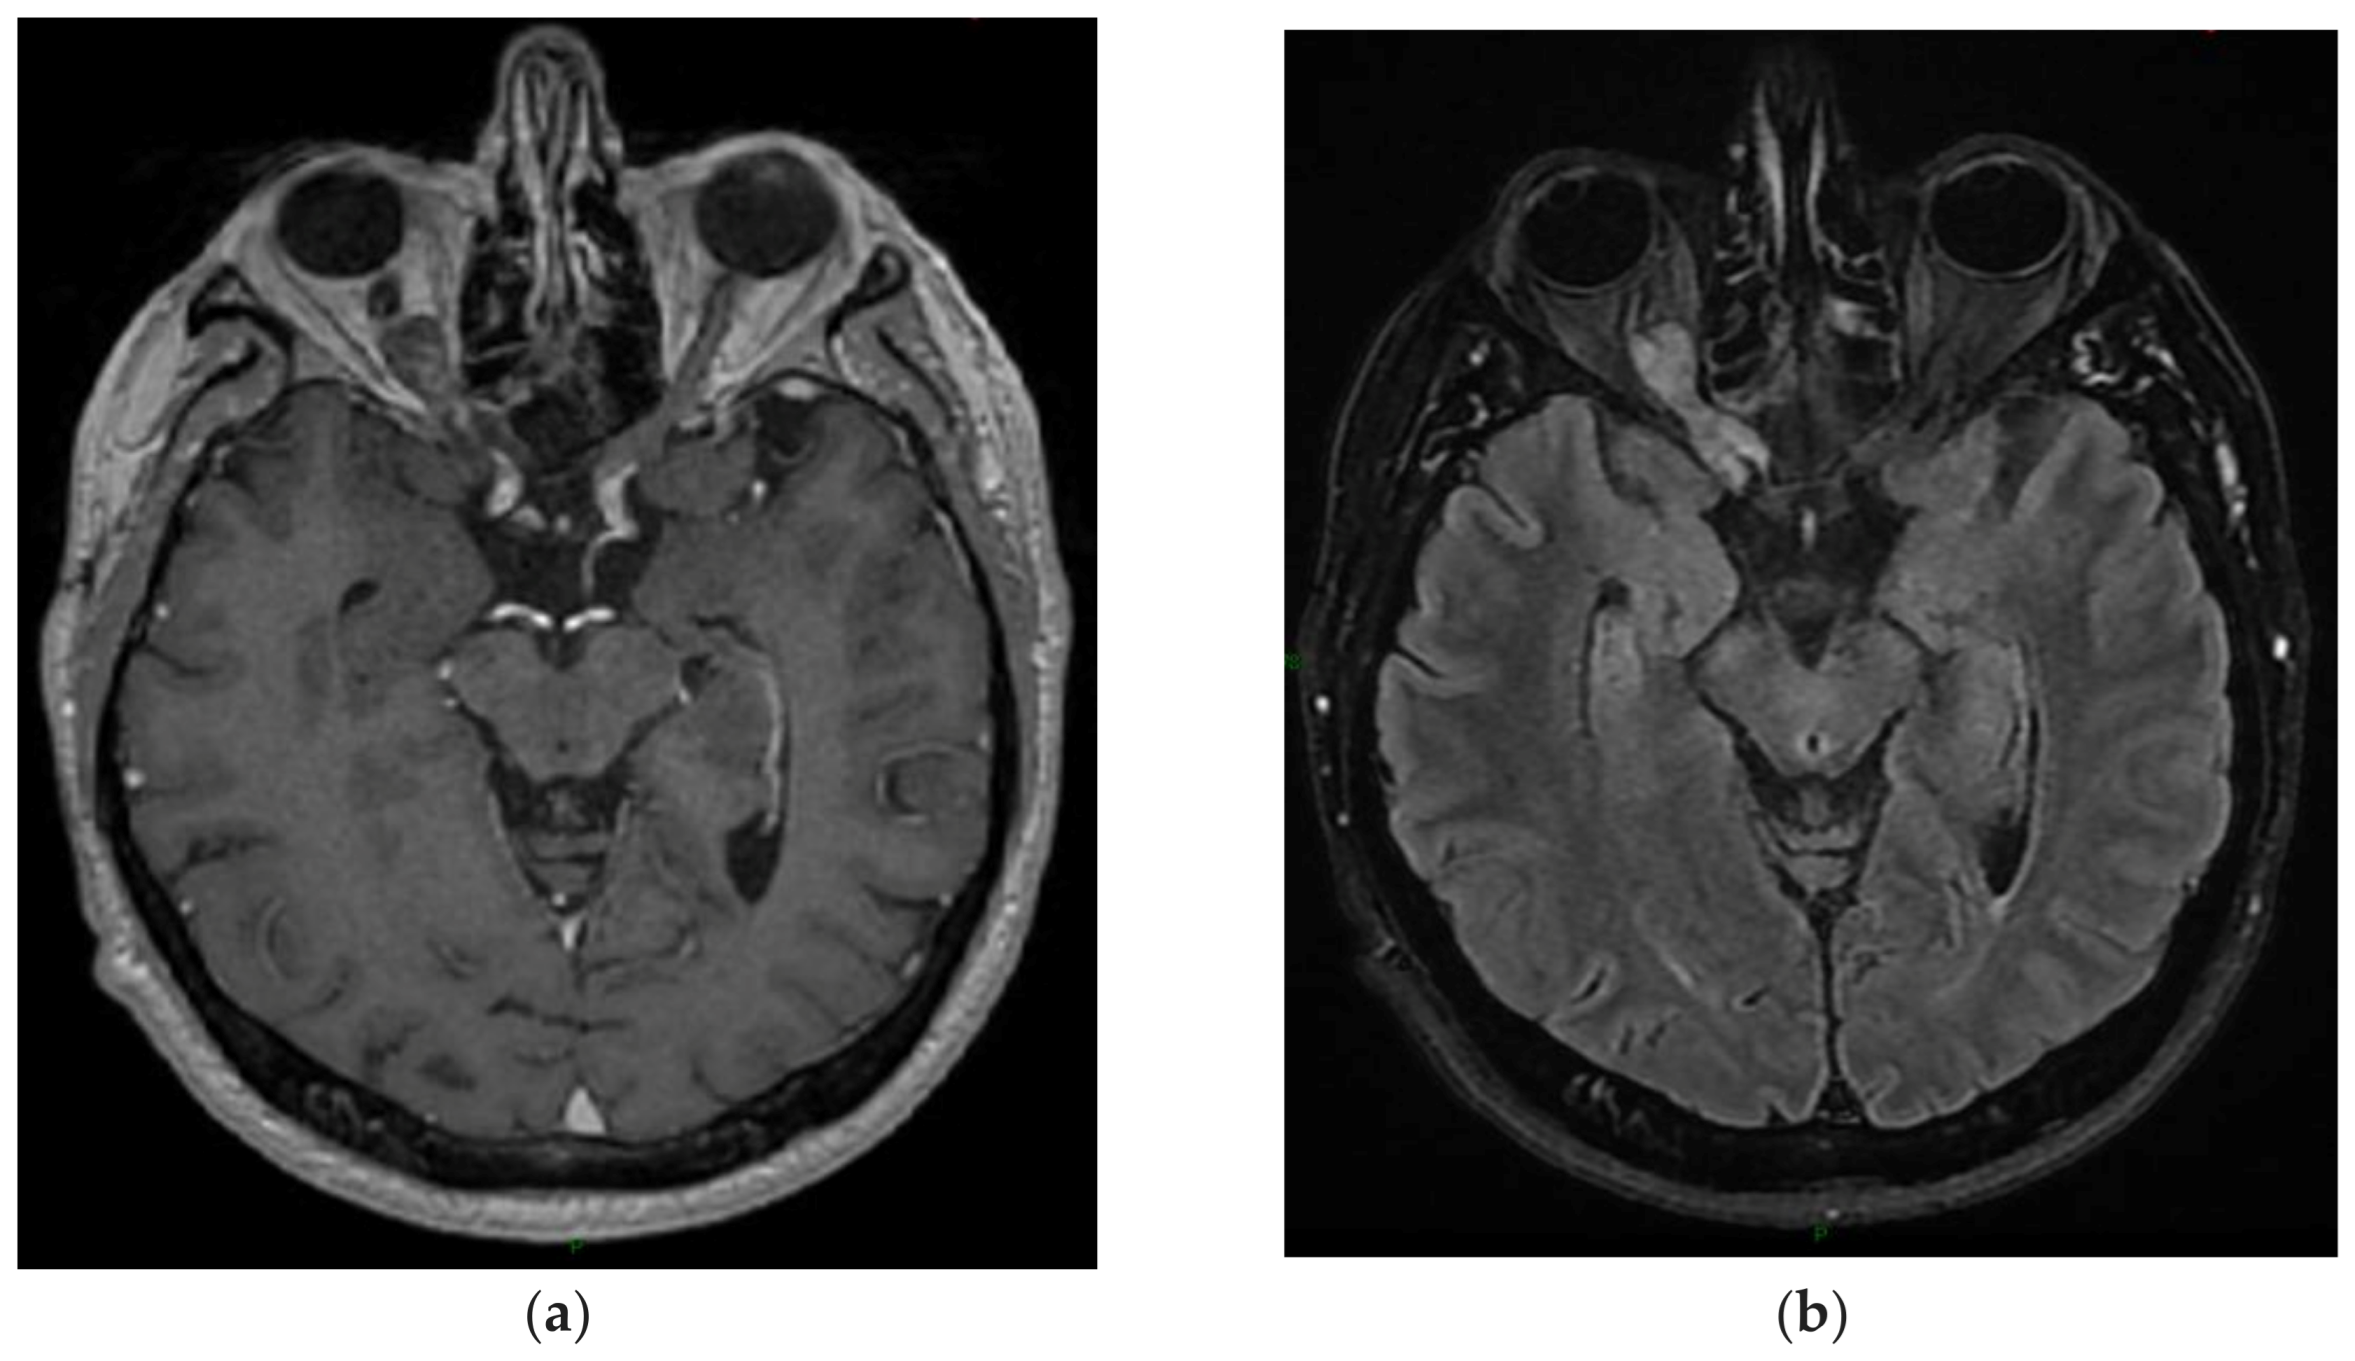

2.1. Dysplastic Cerebellar Gangliocytoma (Lhermitte–Duclos Disease, DCG)